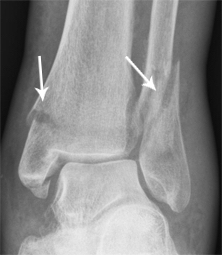

Fractura de tobillo Tobillo roto

Una fractura de tobillo es la rotura de uno o varios huesos del tobillo. En muchos casos se rompe el hueso de la pantorrilla, pero también pueden producirse roturas en otras partes del tobillo. En casos graves, los huesos se rompen en varios lugares al mismo tiempo.

El diagnóstico se confirma mediante una exploración física y una radiografía.